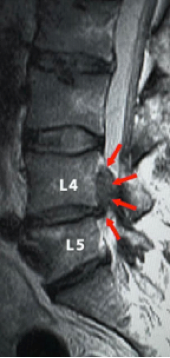

Disc prolapse most commonly affects the lumbar spine (lower back) — particularly at the L4–L5 and L5–S1 levels — but can also occur in the cervical spine (neck).

MRI scans – the most accurate test for visualizing discs and nerves

The gold standard imaging for disc prolapse is MRI:

• MRI clearly shows the disc, its position, the degree of prolapse, and the exact nerve or spinal cord being compressed

• It identifies the level and type of prolapse — contained, extruded, or sequestered

• Essential for surgical planning and confirming the diagnosis